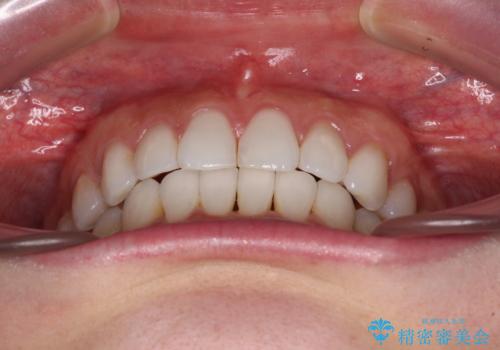

- 前歯のデコボコを気にして来院された患者様です。

海外に留学をされており、卒業後はしばらく日本にいるものの、再び就職のため出国するとのことでした。

定期的に日本に戻ってくる予定であるため、来院頻度の少ないインビザラインにて矯正治療を行うこととしました。

歯列不正が軽度であり、インビザラインの装着時間を遵守してくださったため、日本と海外を行き来しながらも2年弱でしっかりと仕上げることができました。